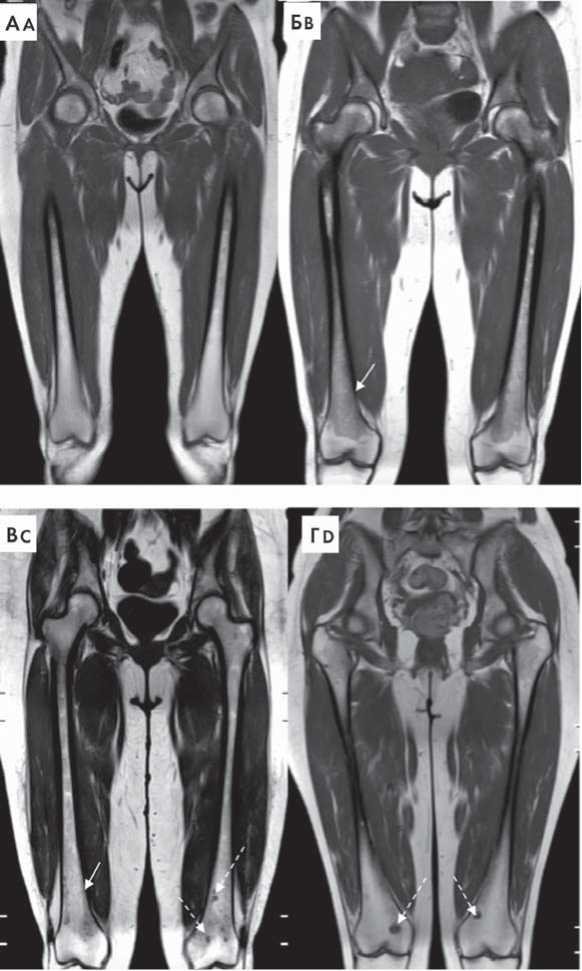

Рисунок 1. Типы поражения костного мозга при ММ на примере бедренных костей в режиме Т1-ВИ. А — нормальный костный мозг, Б — диффузный тип поражения костного мозга (указан сплошной стрелкой), В — диффузно-очаговый тип поражения костного мозга (диффузная инфильтрация указана сплошной стрелкой, очаги поражения указаны прерывистой стрелкой), Г — очаговый тип инфильтрации костного мозга (очаги поражения указаны прерывистой стрелкой)

Figure 1. Bone marrow infiltration patterns in MM patients, femur, T1WI. A — intact bone marrow, B — diffuse bone marrow infiltration (solid arrow), C — diffuse and focal infiltration (diffuse infiltration marked by solid arrow, foci — by dashed arrow), D — focal infiltration (dashed arrow)